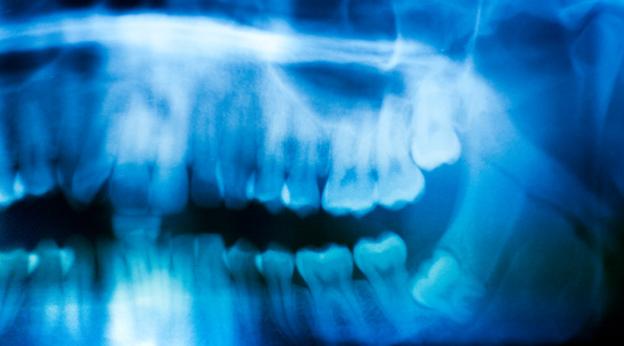

Do you know all impacted wisdom teeth are not created equal? Yes, there are four types of impacted wisdom teeth. When a wisdom tooth breaks through the gum is called as eruption. However, a wisdom tooth not always grows in the right position. They may grow in different angles causing damages to other teeth. When a wisdom tooth does not fully grow is often referred to impaction. It is usually unable to break through the gums because there isn’t enough room.

Impacted wisdom teeth are classified based on the nature of their growth.

Bony impaction – In this type of impaction, the wisdom teeth can’t able to grow out of the bone. So, this type of infection is difficult to remove as the tooth would have not been even reached the soft tissue.

Soft tissue impaction – When the wisdom tooth tries to come out, it gets stuck in the gum tissue, pushing the second molar. Although you cannot see the impacted tooth, it can still hurt and disrupt dental alignment.

Partial eruption – A third molar is impacted when it is obstructed by a nearby tooth and cannot completely erupt. However, cleaning becomes difficult as it cannot be reached with a toothbrush. This type of impaction requires cheap wisdom teeth removal Sydney as they are vulnerable to dental decay and gum disease.

Horizontal impaction – It is the most painful and complicated type of impaction as it has grown sideways within the jawbone. Instead of growing vertically towards the gum line, the tooth is likely growing directly toward existing teeth.

Mesial/Distal impaction - When a wisdom tooth grows toward the existing teeth it pushes these teeth out of place and leads to discomfort and pain. In contrast, a distal impaction describes a tooth that is angled away from other teeth.